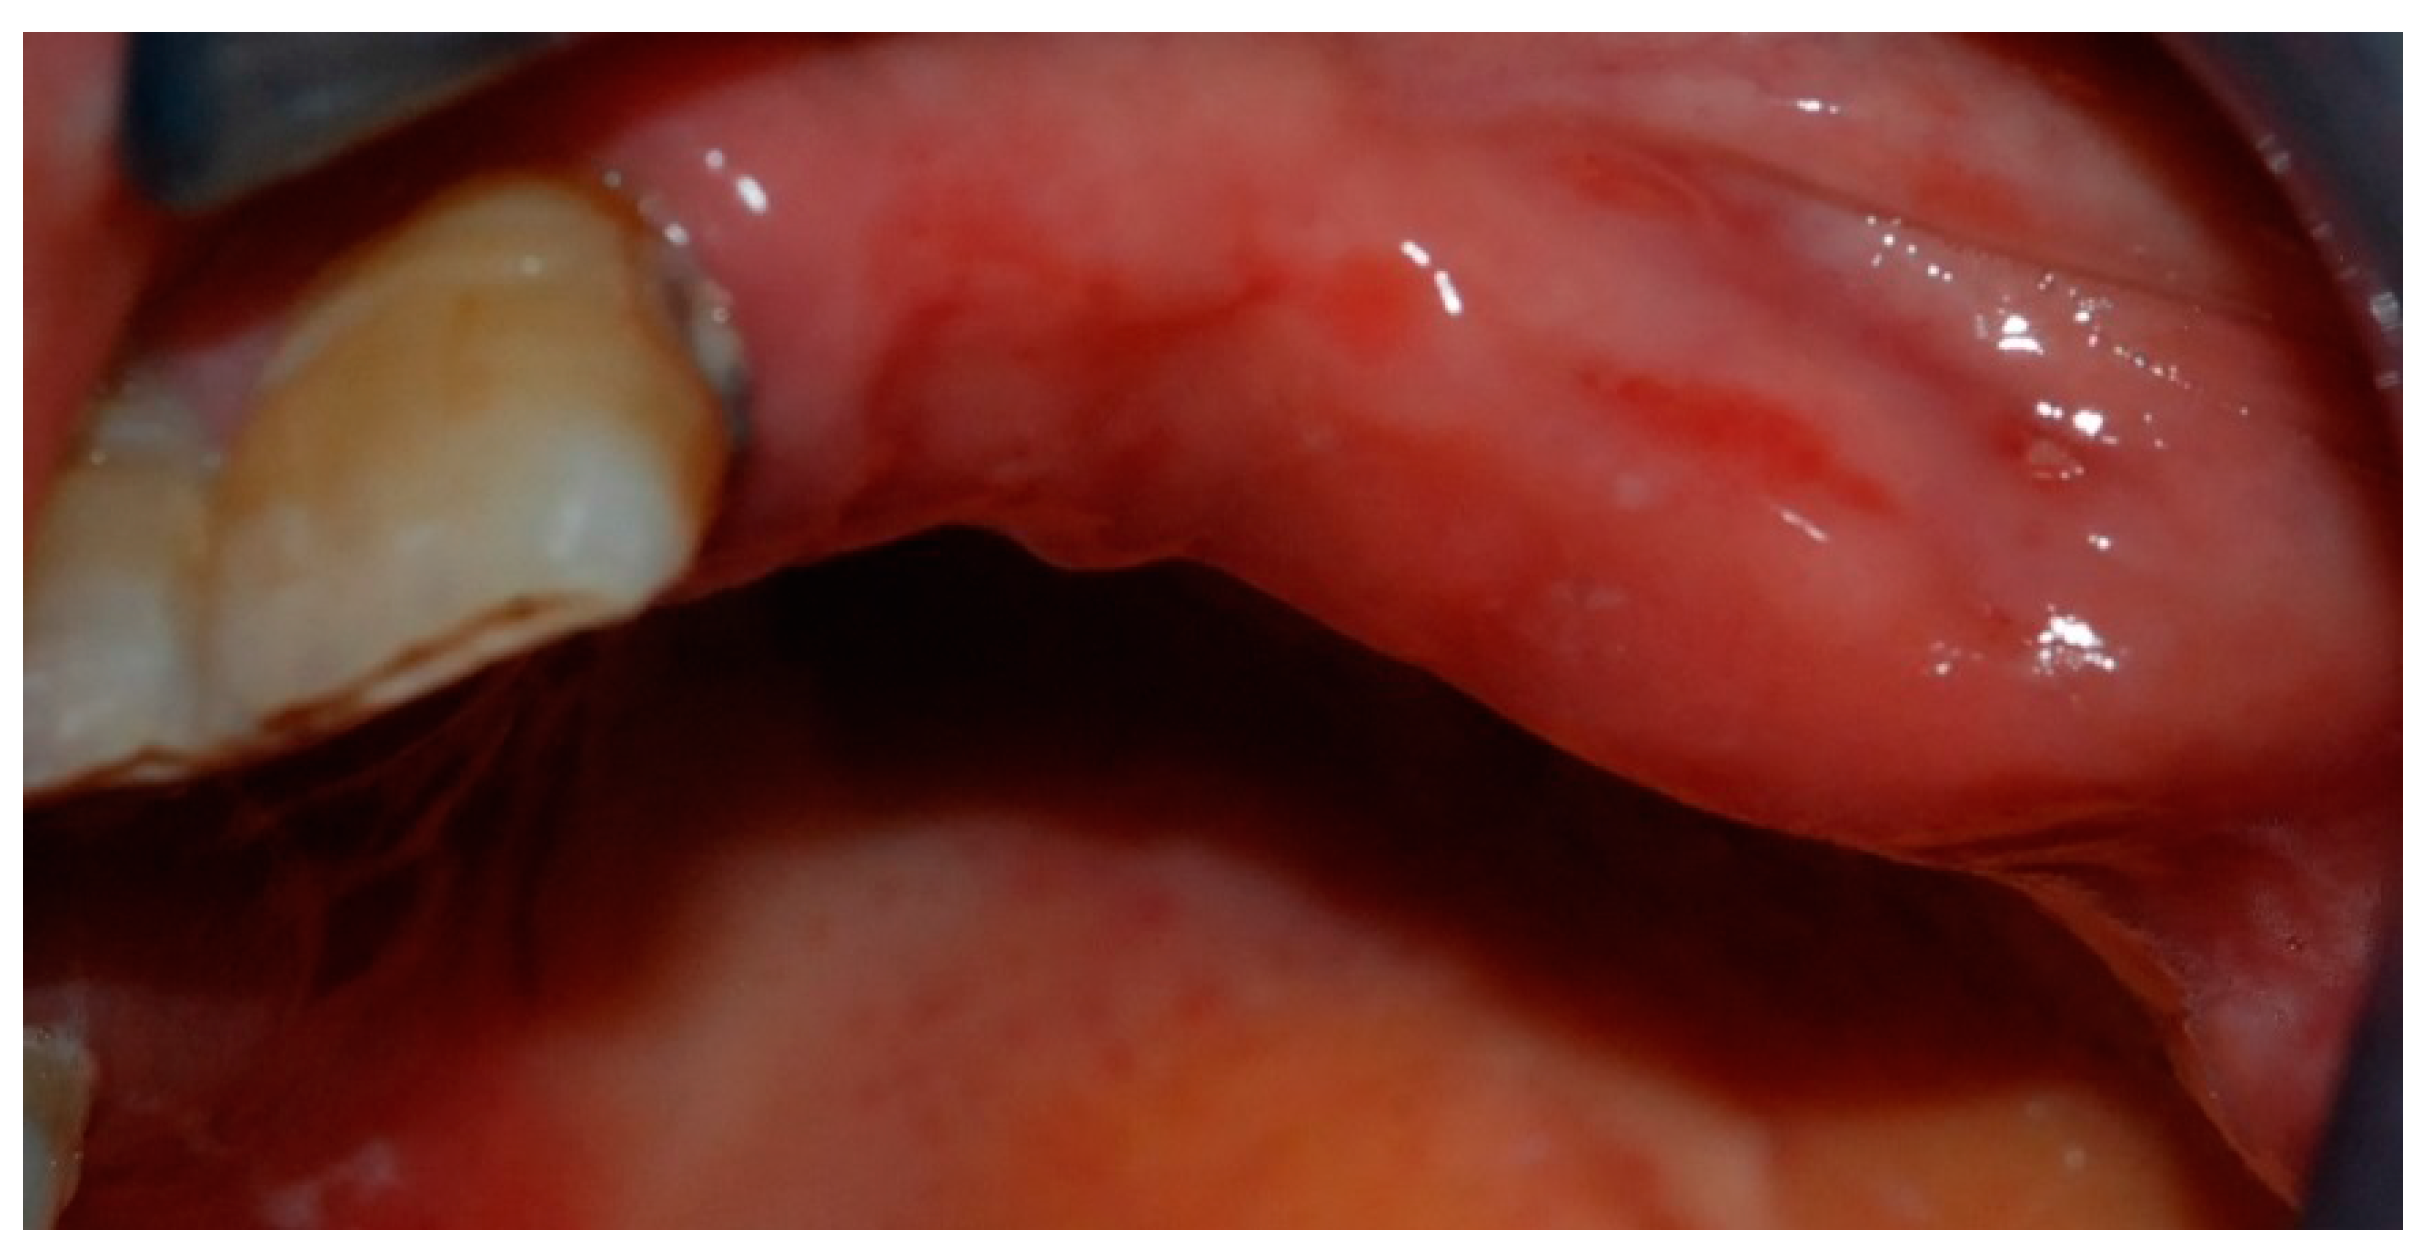

- Bedogni, A.; Fedele, S.; Bedogni, G.; Scoletta, M.; Favia, G.; Colella, G.; Agrillo, A.; Bettini, G.; Di Fede, O.; Oteri, G.; et al. Staging of osteonecrosis of the jaw requires computed tomography for accurate definition of the extent of bony disease. Br. J. Oral Maxillofac. Surg. 2014, 52, 603–608. [Google Scholar] [CrossRef] [PubMed]

- Fedele, S.; Bedogni, G.; Scoletta, M.; Favia, G.; Colella, G.; Agrillo, A.; Bettini, G.; Di Fede, O.; Oteri, G.; Fusco, V.; et al. Up to a quarter of patients with osteonecrosis of the jaw associated with antiresorptive agents remain undiagnosed. Br. J. Oral Maxillofac. Surg. 2015, 53, 13–17. [Google Scholar] [CrossRef] [PubMed]